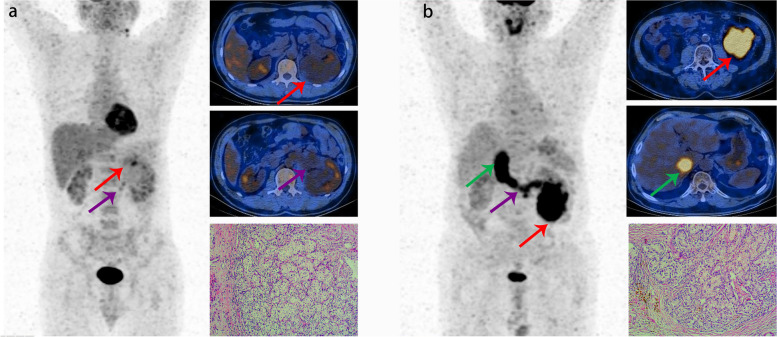

As shown in Table 3, the diagnostic value of 18F-FDG PET/CT imaging for the level of VTT (early VTT or advanced VTT) was further analyzed in 59 true-positive cases with VTT, including 49 early VTT and 10 advanced VTT. The sensitivity, specificity, accuracy, PPV, and NPV were 70.0, 100.0, 94.9, 100.0, and 94.2%, respectively. Kappa value between PET/CT and clinically confirmed results was 0.795 in diagnosing the level of VTT. The typical cases are shown in Fig. 2.

Fig. 2.

a Images in a 57-year-old male with ccRCC demonstrate left renal vein tumor thrombus (red arrows), with VTT SUVmax of 4.5 (left image: anterior maximum intensity projection image obtained at 18F-FDG PET; right upper image: axial contrast-enhanced MRI image; right middle image: axial contrast-enhanced CT image; right lower image: axial fused PET/CT image). b Images in a 55 year-old male with ccRCC demonstrate left renal vein tumor thrombus (red arrow), inferior vena cava tumor thrombus (blue arrow), and tumor thrombus in the right atrium (green arrows), with VTT SUVmax of 5.7 (left image: anterior maximum intensity projection image obtained at 18F-FDG PET; right upper image: axial contrast-enhanced MRI image; right middle image: axial contrast-enhanced CT image; right lower image: axial fused PET/CT image)